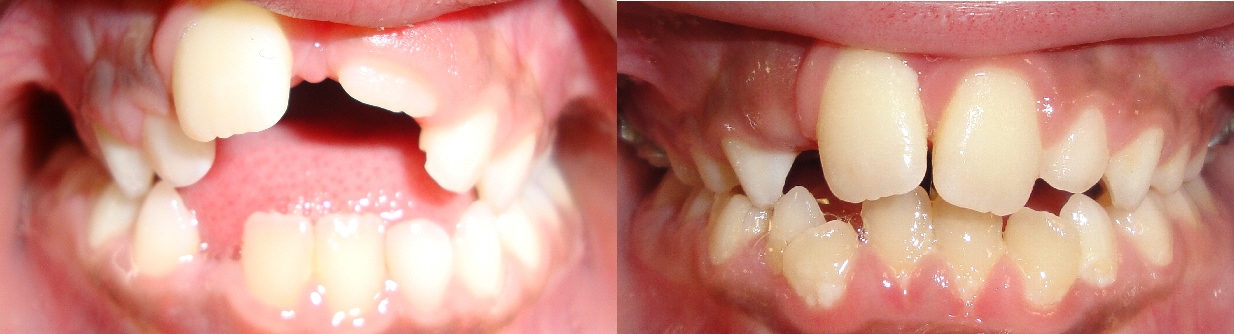

Chansomally

- Problem: Impacted Teeth

- Treatment: Braces with Surgical Exposure of Teeth